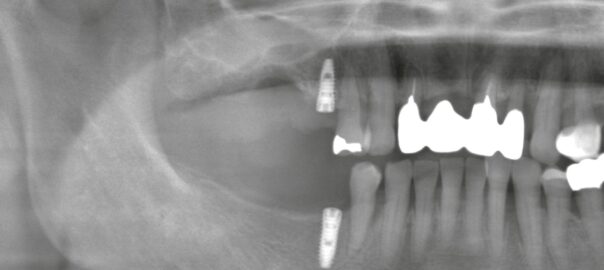

インプラント治療は痛い?腫れはどのくらい?術後の痛みはいつまで続く?【よくある質問に歯科医が回答】

昨日は、右側の上下にインプラント治療を行いました。 そのうち1本は「抜歯即時インプラント」(抜歯と同日にインプラントを埋入する方法)で実施しています。 インプラントの相談で、特に多い質問がこちらです。 * インプラント治 … 続きを読む インプラント治療は痛い?腫れはどのくらい?術後の痛みはいつまで続く?【よくある質問に歯科医が回答】